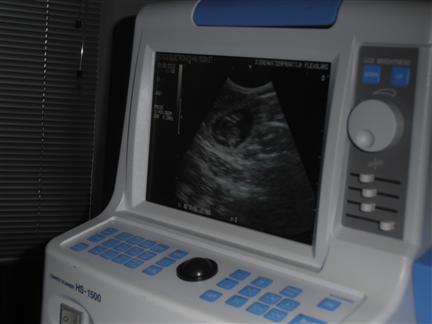

| FEEST, Fleur is drachtig, hier zie je één van de pupjes in wording |

in de donkere vlek (het vruchtwater) zie je een puppy |